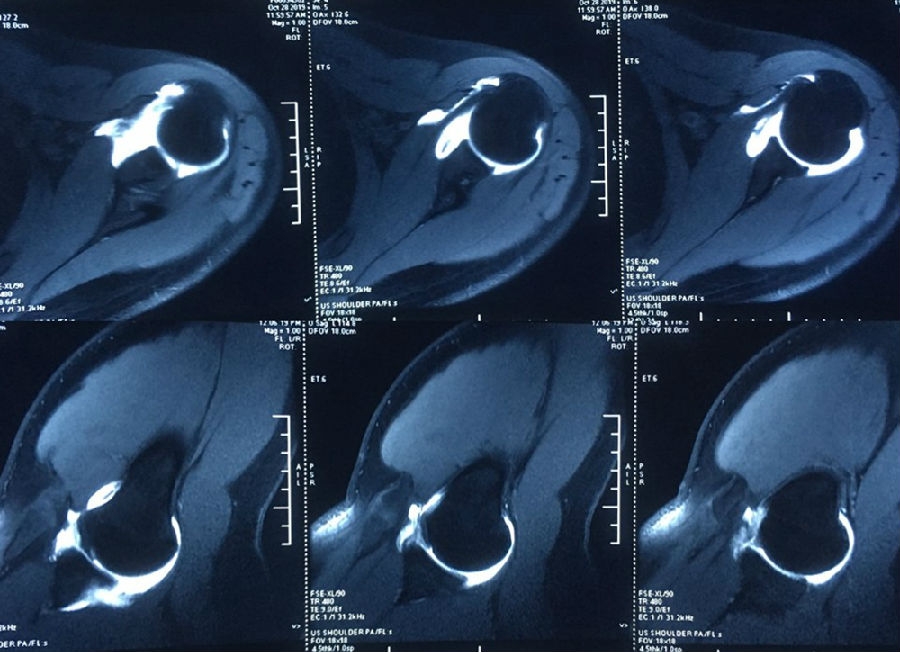

图39 此次复发脱位MR评估

图40 影像学评估

双侧CT三维扫描显示:D=34mm,d=3mm,d/D=肩胛盂骨缺损9%;GT=25.2mm,HIS=30mm。

该患者为轨迹外Hill-Sachs损伤,需要做bankart修补,同时轨迹外做remplissage手术。